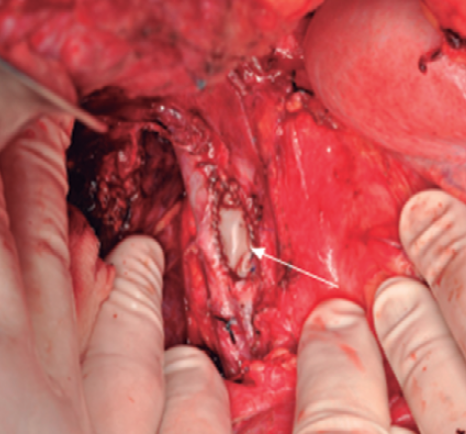

Guillermo Rencoret Palma, Marcelo Vivanco Lacalle, Felipe Andrés Castillo Henriquez, Giancarlo Schippacasse, Xabier De Aretxabala Urquiza, Victor Bianchi, Juan Hepp, Horacio Rios

|